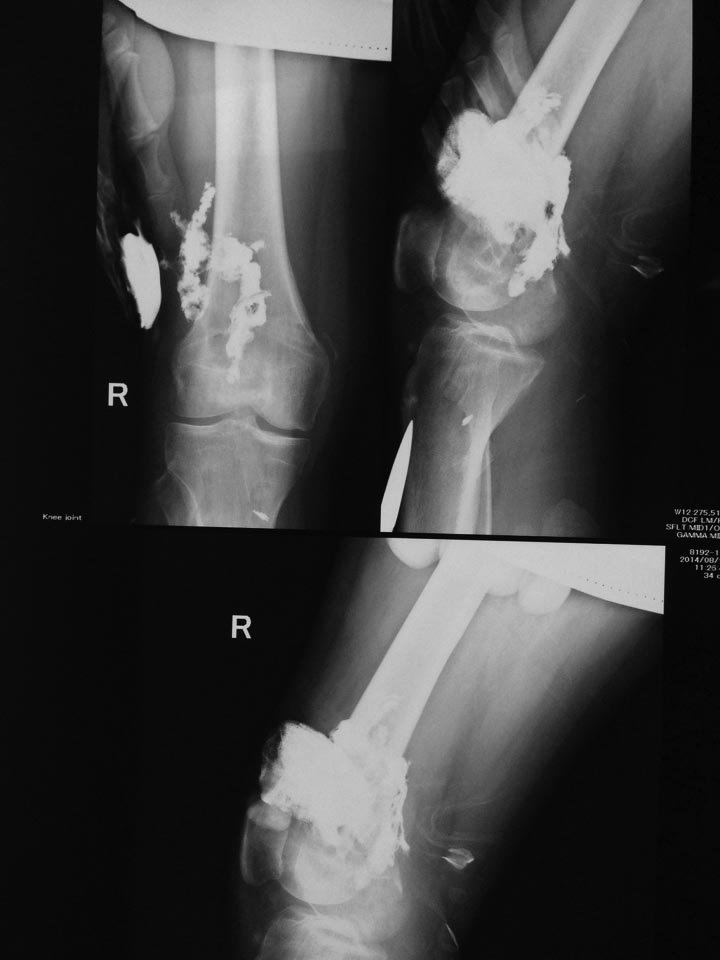

В понедельник сделали фистулографию и получили вот такую картину.

В экстренном порядке взяли на ревизию, и тут все началось - гнойные затеки по всему бедру, по всем костно-мышечным каналам бедра до в/3, книзу доходит до заднего отдела сустава.

В общей сложности, наверное, было эвакуировано 0,5-1 л гноя. Из наружного отдела «вывалились» пины, по объему намного меньше, чем изначальный, думаю, можно это считать нормальным, так как они «саморассасывающиеся».

КТ после операции.

Есть остеопороз, но явного остеомиелита не наблюдается.